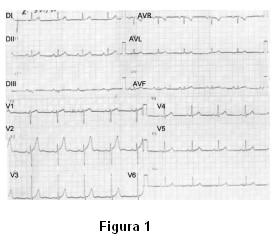

Electrocardiograma (ECG): ritmo sinusal de 70 cpm, P y PR normales, supradesnivel del segmento ST de 1 mm, supracóncavo con ondas T acuminadas de V1 a V3 (figura 1).